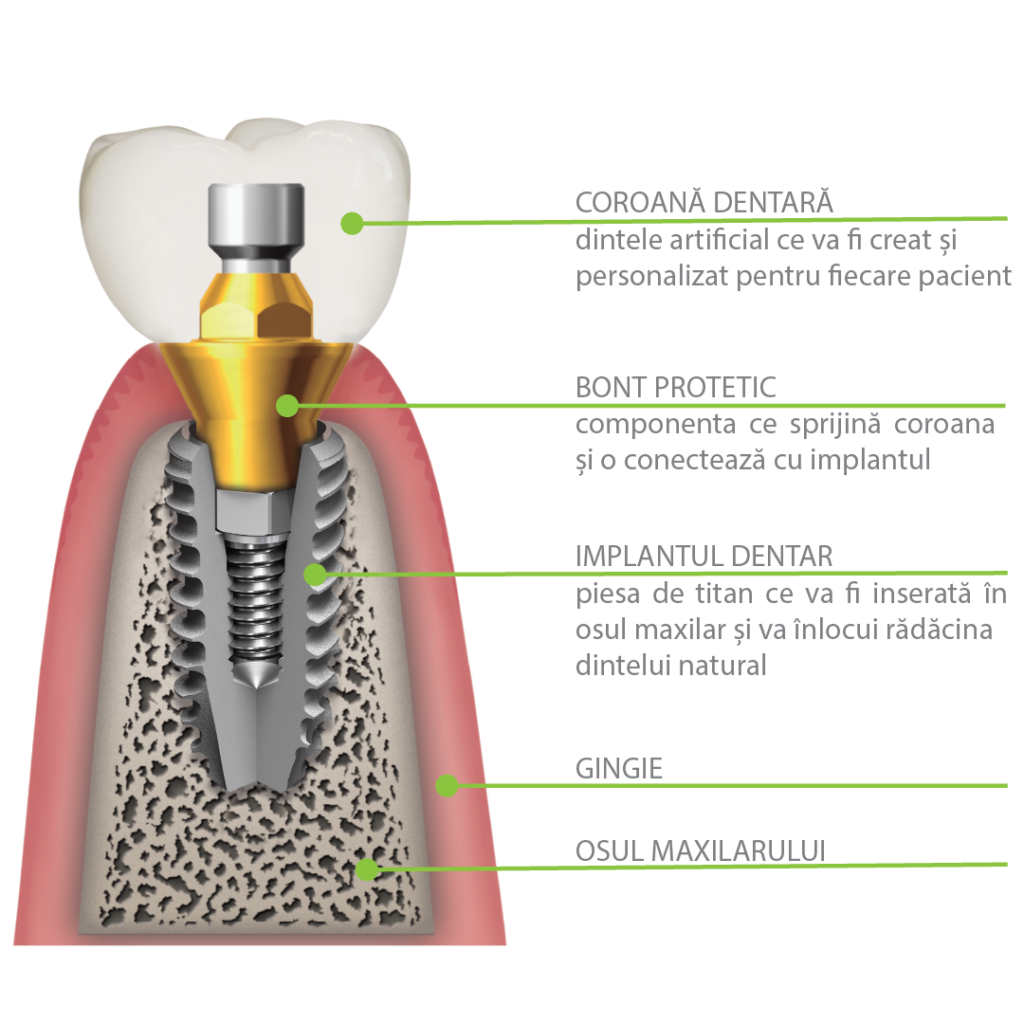

COMPONENTELE IMPLANTULUI DENTAR:

Implantul Dentar: confecționat din titan biocompatibil și durabil, permite integrarea solidă în țesutul osos prin intermediul procesului de osteointegrare. Este inserat chirurgical în osul maxilar sau mandibular și acționează ca o rădăcină artificială, oferind suport robust pentru celelalte componente.

Bontul: Bontul, conectat la implant după integrarea acestuia în os, creează legătura dintre implant și coroană. Acest element de legătură joacă un rol esențial în transmiterea forțelor masticatorii de la coroană către implant, contribuind la distribuirea uniformă a presiunii și asigurând o stabilitate solidă. Bonturile pot varia în funcție de necesitățile fiecărui pacient și sunt concepute pentru a crea o bază solidă pe care coroana dentară va fi ulterior fixată.

Coroana: Reprezintă partea vizibilă a dintelui, plasată deasupra bontului. Este realizată din materiale durabile și estetice, precum ceramică sau zirconiu, pentru a se potrivi cu aspectul natural al dinților vecini. Coroanele sunt confecționate în laboratoare dentare, având în vedere aspectul individual al fiecărui pacient. Aceasta este proiectată să se potrivească perfect în cavitatea orală, redând un zâmbet estetic și o funcțional.